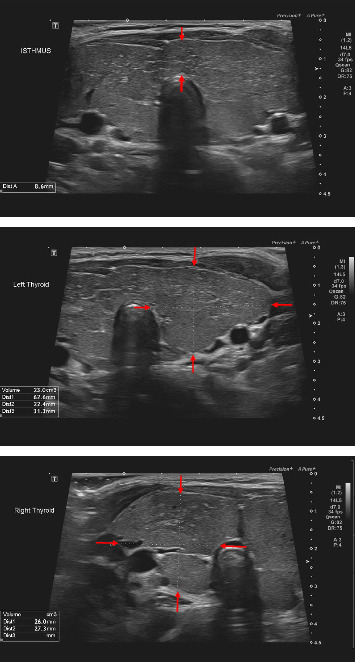

甲状腺单激素生成障碍是由单基因缺陷引起的遗传性甲状腺功能减退症,在绝大多数情况下,在甲状腺激素的生物合成。它通常与甲状腺肿大有关,容易形成结节。我们提出了一个卡塔尔病人忽视诊断甲状腺激素生成障碍由于甲状腺球蛋白基因突变。一名10.5岁男孩自4岁起接受先天性甲状腺功能减退的随访。新生儿筛查确诊,实验室甲状腺功能检查证实;然而,没有做进一步的检查来了解潜在的原因。他的父母是近亲,有甲状腺功能减退的家族史。患者服药及随访不遵医嘱,大部分时间促甲状腺激素在5 mIU/L以上。经检查,他几个月前患了甲状腺肿。父亲承认在出生时就有,但在左旋甲状腺素治疗后消失了。分子遗传学结果显示,在甲状球蛋白基因中存在C . 4426t . b> .C, p.Cys1476Arg纯合子变异。这种变异以前仅在中东地区的5例患者中报道过。确定先天性甲状腺功能减退症的病因对家庭咨询和长期治疗具有重要意义。

Thyroid dyshormonogenesis is an inherited hypothyroidism caused by a monogenic defect, in the vast majority of cases, in thyroid hormone biosynthesis. It is commonly associated with thyroid enlargement which is vulnerable to nodule formation. We present a Qatari patient with an overlooked diagnosis of thyroid dyshormonogenesis due to thyroglobulin gene mutation. A 10.5-year-old boy has been following up for congenital hypothyroidism since the age of 4 years. He was diagnosed by newborn screening that was confirmed by laboratory thyroid function testing; however, no further workup was done to understand the underlying cause. He was born to consanguineous parents with a family history of hypothyroidism. The patient was not adherent to his medication and follow-up visits, and thyroid-stimulating hormone was above 5 mIU/L most of the time. On examination, he had a goiter that developed a few months ago. The father admitted that it was there at birth but disappeared with levothyroxine therapy. Molecular genetics revealed a homozygous c.4426T > C, p.Cys1476Arg variant in the thyroglobulin gene. This variant was only previously reported, in the Middle East region, in five patients. Determination of congenital hypothyroidism underlying etiology is important for family counseling and long-term management.